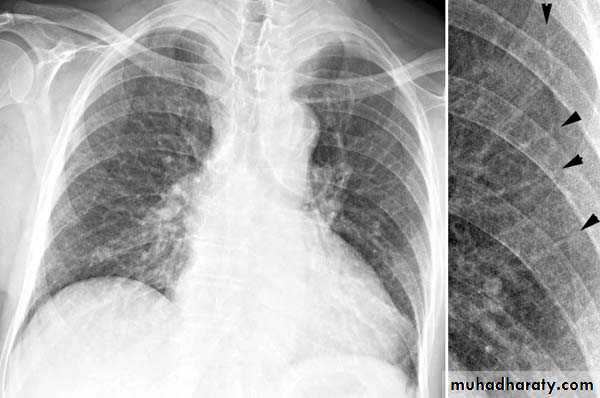

TB of the lung

Tuberculosis encompasses an enormously wide disease spectrum affecting multiple organs and body systems predominantly caused by the organism Mycobacterium tuberculosisPulmonary manifestations of tuberculosis are varied and depend in part whether the infection is primary or post-primary. The lungs are the most common site of primary infection by tuberculosis and are a major source of spread of the disease .

Radiographic featuresprimary pulmonary tuberculosis

1.the initial focus of infection can be located anywhere within the lung and has non-specific appearances ranging from too small to be detectable, to patchy areas or consolidation or even lobar consolidation in RT upper or RT middle lobe . Radiographic evidence of parenchymal infection is seen in 70% of children and 90% of adults called Ghon lesion , +/- ipsilateral hilar or paratracheal Lymph adenopathy usually right sided

( Ghon focus + LAP ) called primary complex.

2.Later In most cases, the infection becomes localized and a caseating granuloma resolve eventually calcifies with or without calcification of the regional LN , Calcification of nodes is seen in 35% of cases . When a calcified node and a calcified Ghon lesion are present, the combination is known as a Ranke complex.

3. Pleural effusions are more frequent in adults .

Post primary TB radiographic appearance

Post-primary pulmonary tuberculosis, also known as reactivation tuberculosis or secondary tuberculosis occurs years later, frequently in the setting of a decreased immune status. In the majority of cases, post-primary TB within the lungs develops in either :

* posterior segments of the upper lobes

*superior segments of the lower lobes

Typical appearance of post-primary TB

1.patchy consolidation or poorly defined linear and nodular opacities in both apices , upper zone in one lung , & lower zone in other lung ( ulternating lesion ) .2. Post-primary infections are far more likely to cavitate with multiple abscess formation & air fluid level more develop in the posterior segments of the upper lobes.

3. Tuberculomas seen in post-primary TB and appear as a well defined rounded mass typically located in the upper lobes .

4. Miliary tuberculosis is uncommon but carries a poor prognosis. It represents haematogenous dissemination of an uncontrolled tuberculous infection. It is seen both in primary and post-primary tuberculosis. Although implants are seen throughout the body, the lungs are usually the easiest location to the image. Miliary deposits appear as 1-3 mm diameter nodules . are uniform in size and uniformly distributed